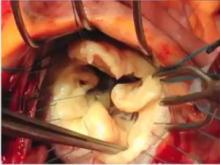

Mitral Clefts, Calcium, and More [1]

Francis Wells of Papworth Hospital, Cambridge, United Kingdom, gives an in-depth talk on the anatomy of the mitral valve and the importance of mitral clefts. Mr. Wells reviews the development of the mitral valve and its saddle shape. He also discusses the treatment of SAM and calcium, and the use of annuloplasty rings.